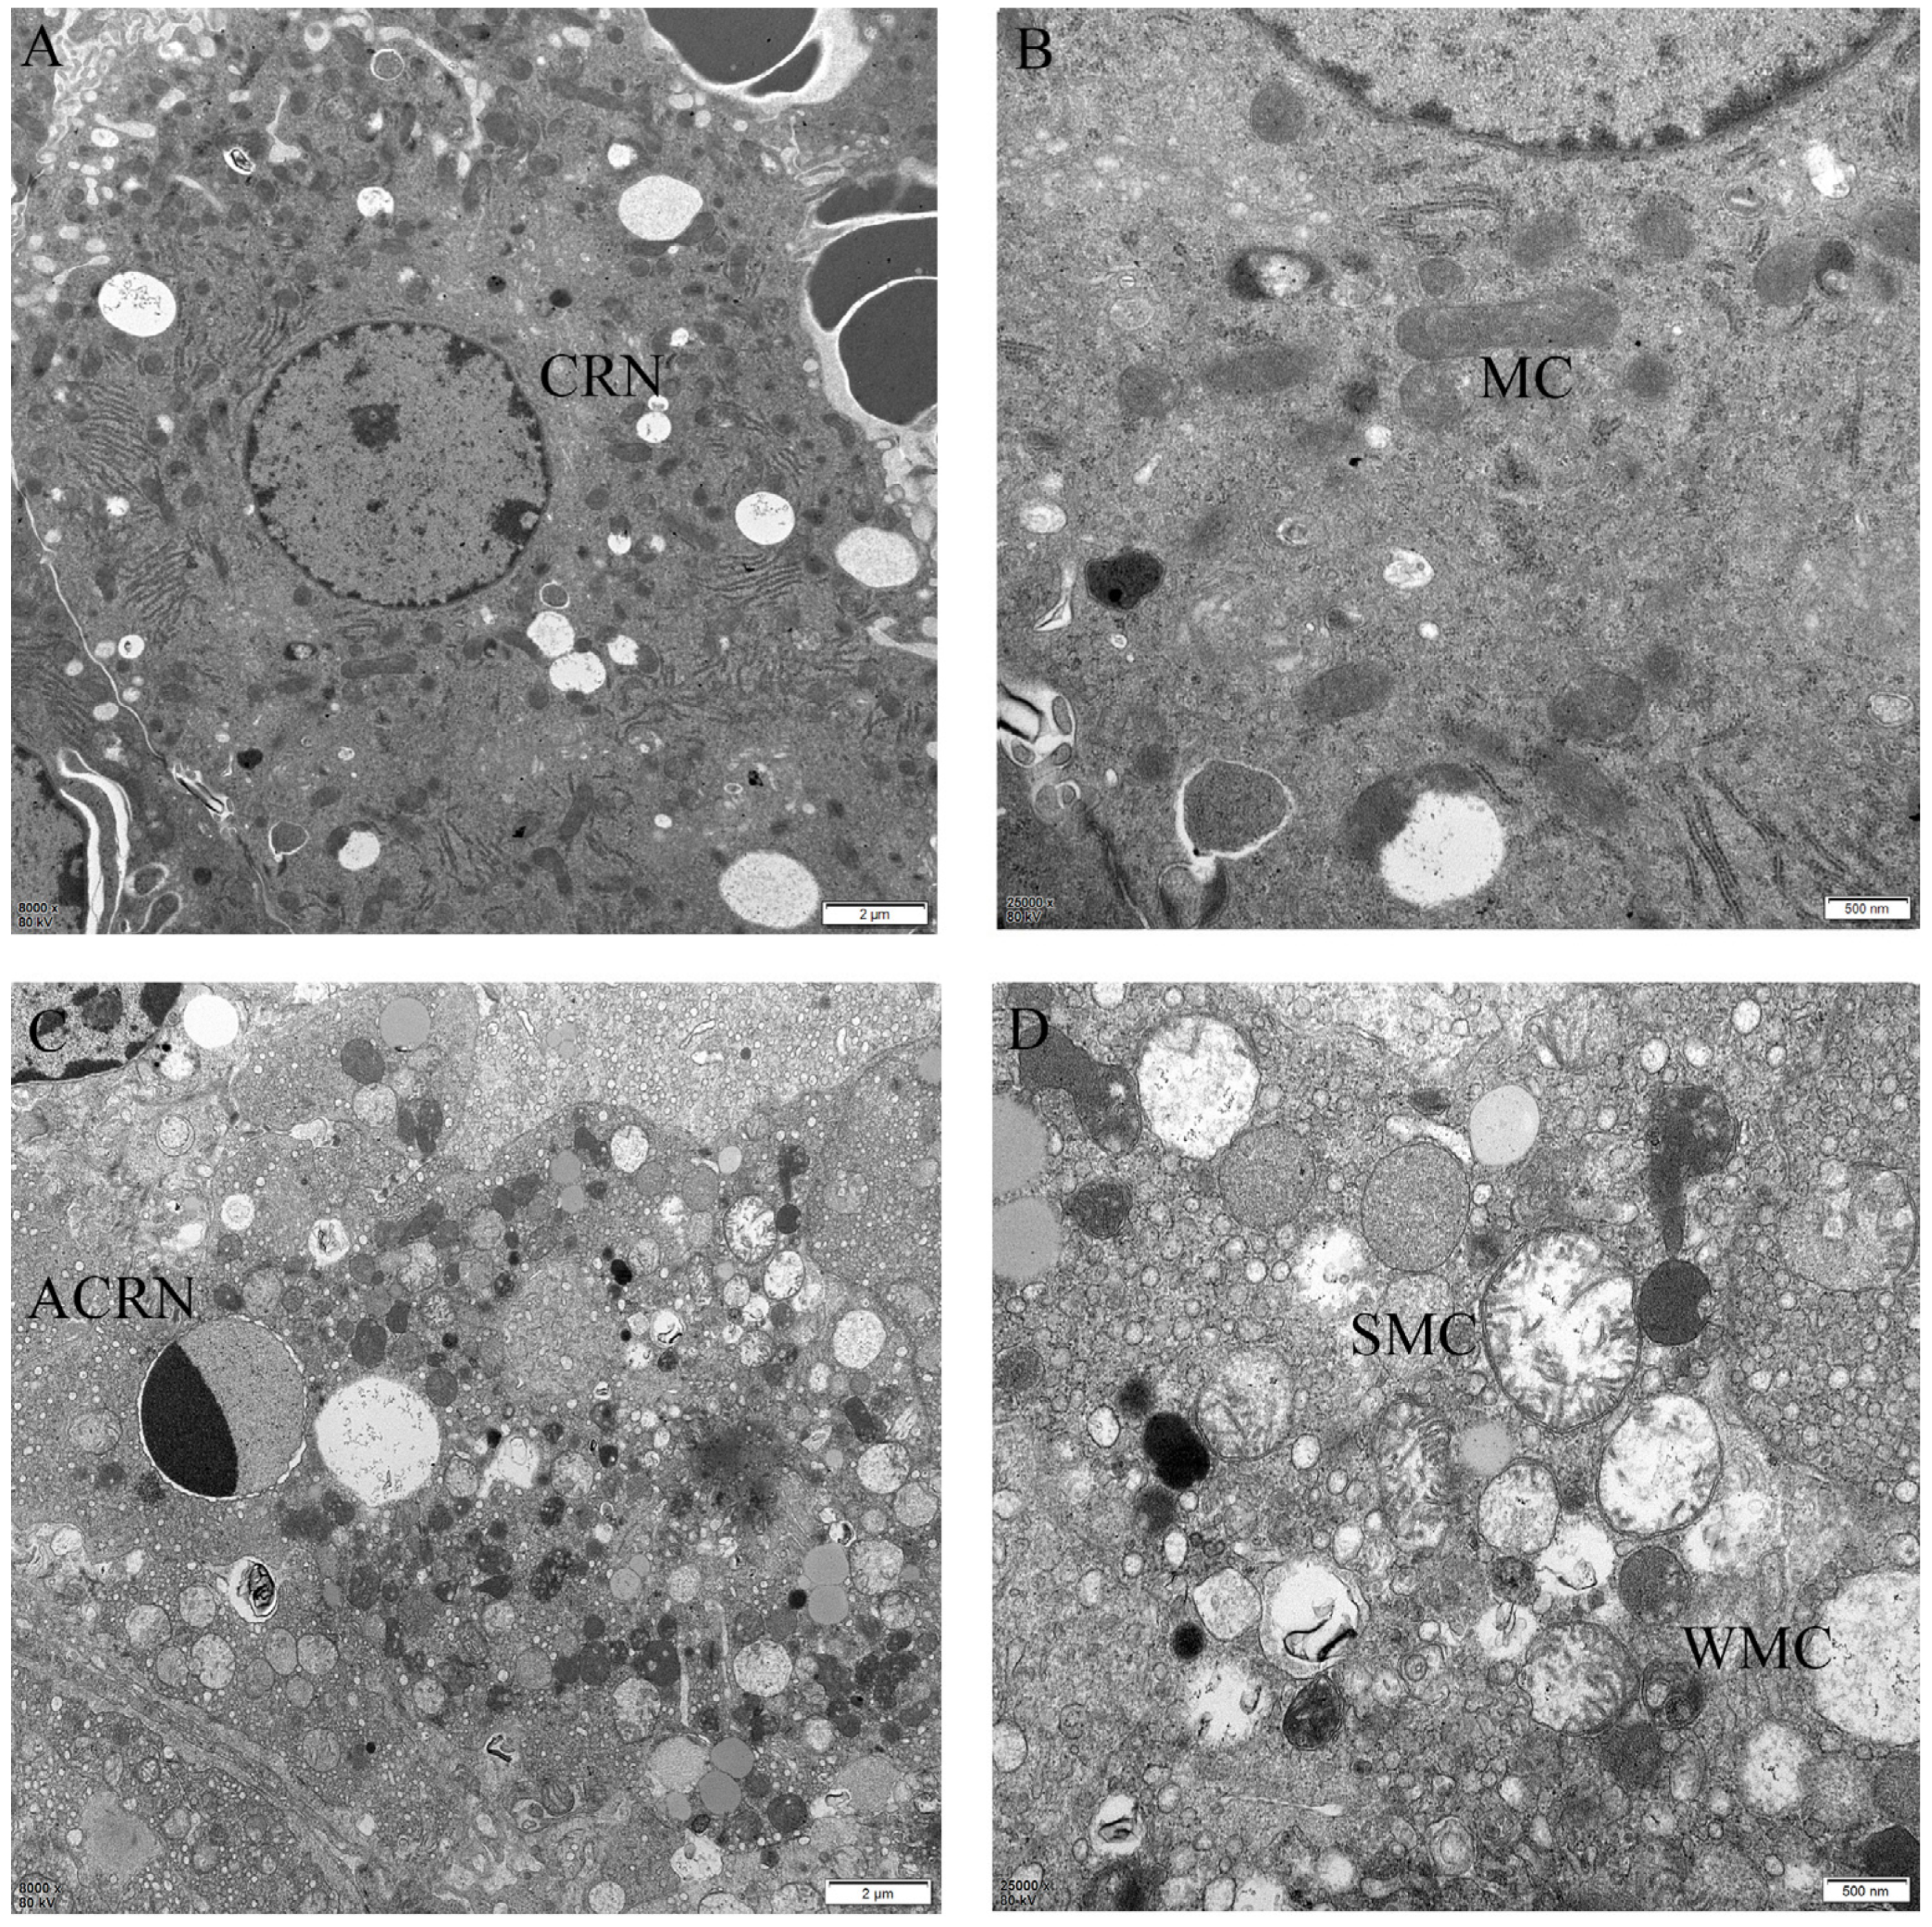

2.4. The Protective Effect of Different Suspensions on the Liver’s Ultrastructure

4.8. Ultrastructural Observation of Liver